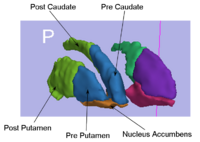

Rule-Based Striatum SegmentationIn this work, we provide software to semi-automate the implementation of segmentation procedures based on expert neuroanatomist rules for the striatum. More... |